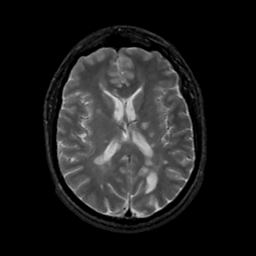

MR Study #14, June 2, 1991 -- Slice #29